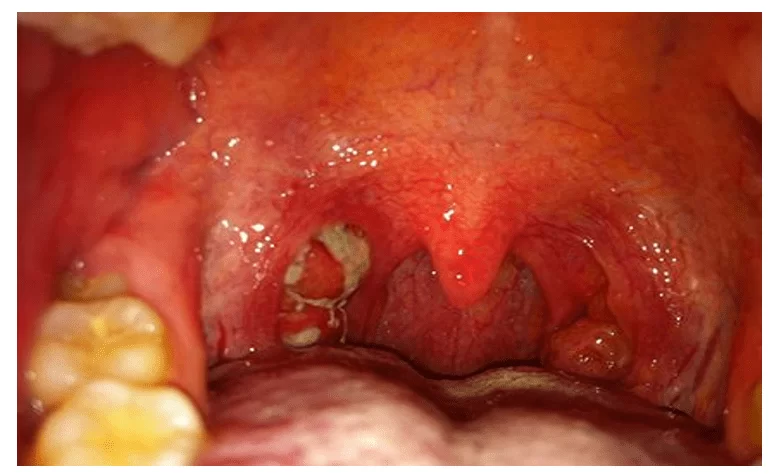

- Painful mouth sores (aphthous stomatitis)

- Sore throat (pharyngitis) without bacterial infection